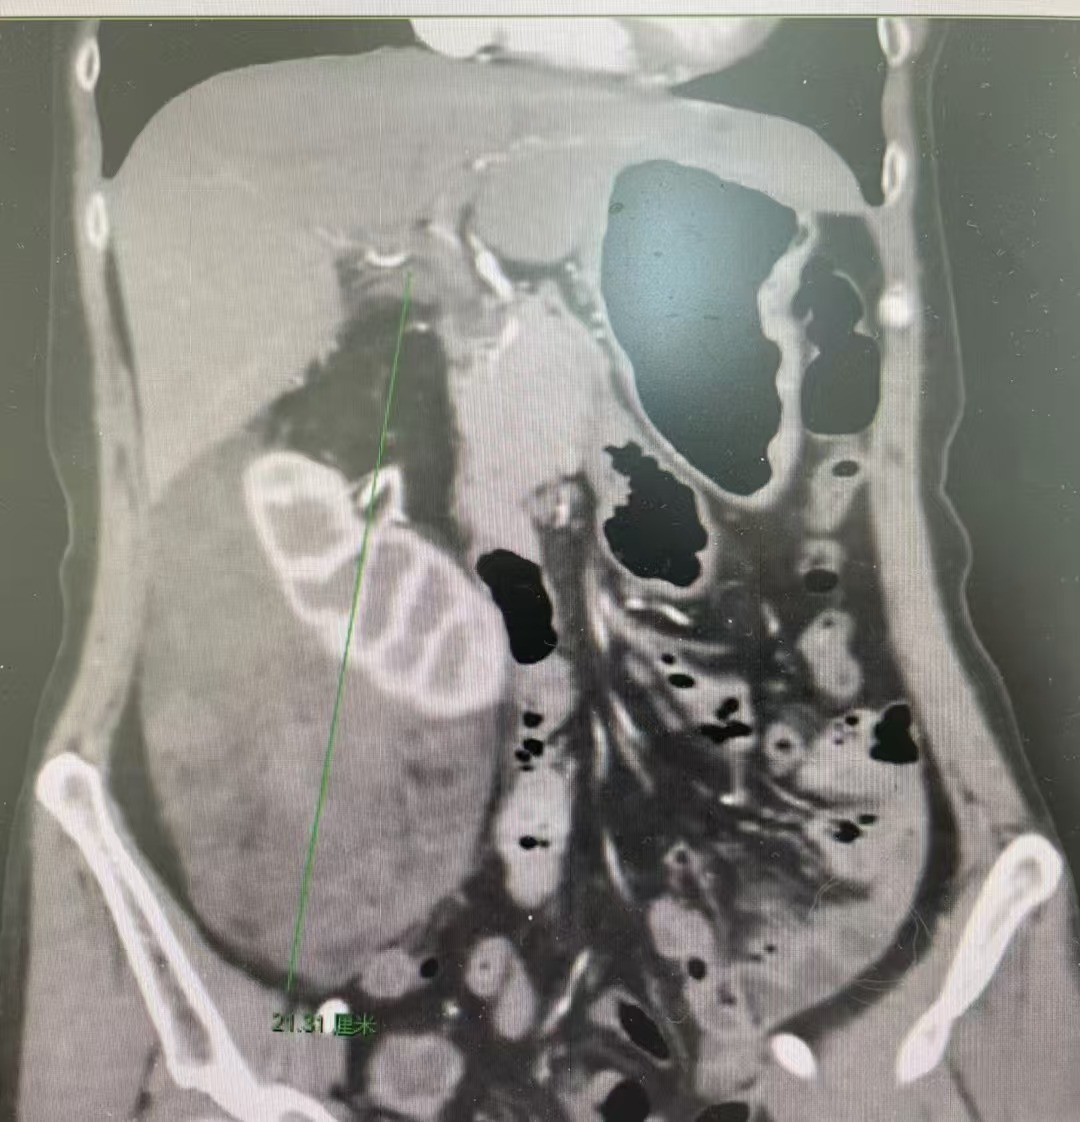

患者刘某,女,57 岁,因右侧腰部疼痛不适 3 天就诊。接诊后,泌尿外科主任医师刘飞立即为患者安排 CT 和肿瘤血管三维重建,检查显示右侧腹膜后巨大肿瘤,上下径 26 cm, 左右径 18 cm, 肿瘤越过中线严重挤压下腔静脉,推压腹主动脉和十二指肠,肿瘤上极挤压肝胆重要解剖结构,下极越过右侧髂外血管;肿瘤与右肾、肾上腺分界不清,来源肾脏可能性大,肿瘤含有两种以上成分可能。

在充分术前准备后,手术按计划进行,术中见巨大肿瘤占据右侧腹腔,肿瘤上缘紧贴肝脏和胆囊,内侧面覆盖完全包绕右肾动静脉,紧贴下腔静脉等大血管。手术由主任医师刘飞主刀,带领团队成员主治医师彭翔等通过细致的解剖,在腔静脉和腹主动脉之间找到右肾动脉,抽丝剥茧般将右肾从肿瘤中剥离出来。在手术室团队的密切配合下,刘飞教授仅用 3 个小时便成功完整地切除了这个长径超过 25 cm 的特大肿瘤。